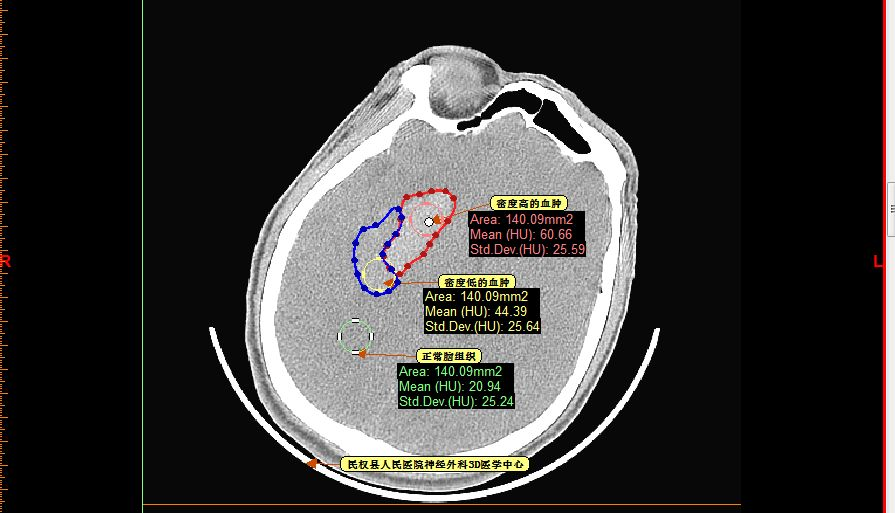

再仔细观察并划定血肿分层区域,可设定血肿为高密度区域、低密度区域,和正常脑组织对比

以红色区域划分为高密度区域、蓝色区域划分为低密度区域

测量各密度区域CT阈值,可见高密度区域(红色区域)CT阈值为60.66,低密度区域(蓝色区域)CT阈值为44.39,正常脑组织区域CT阈值为20.94。